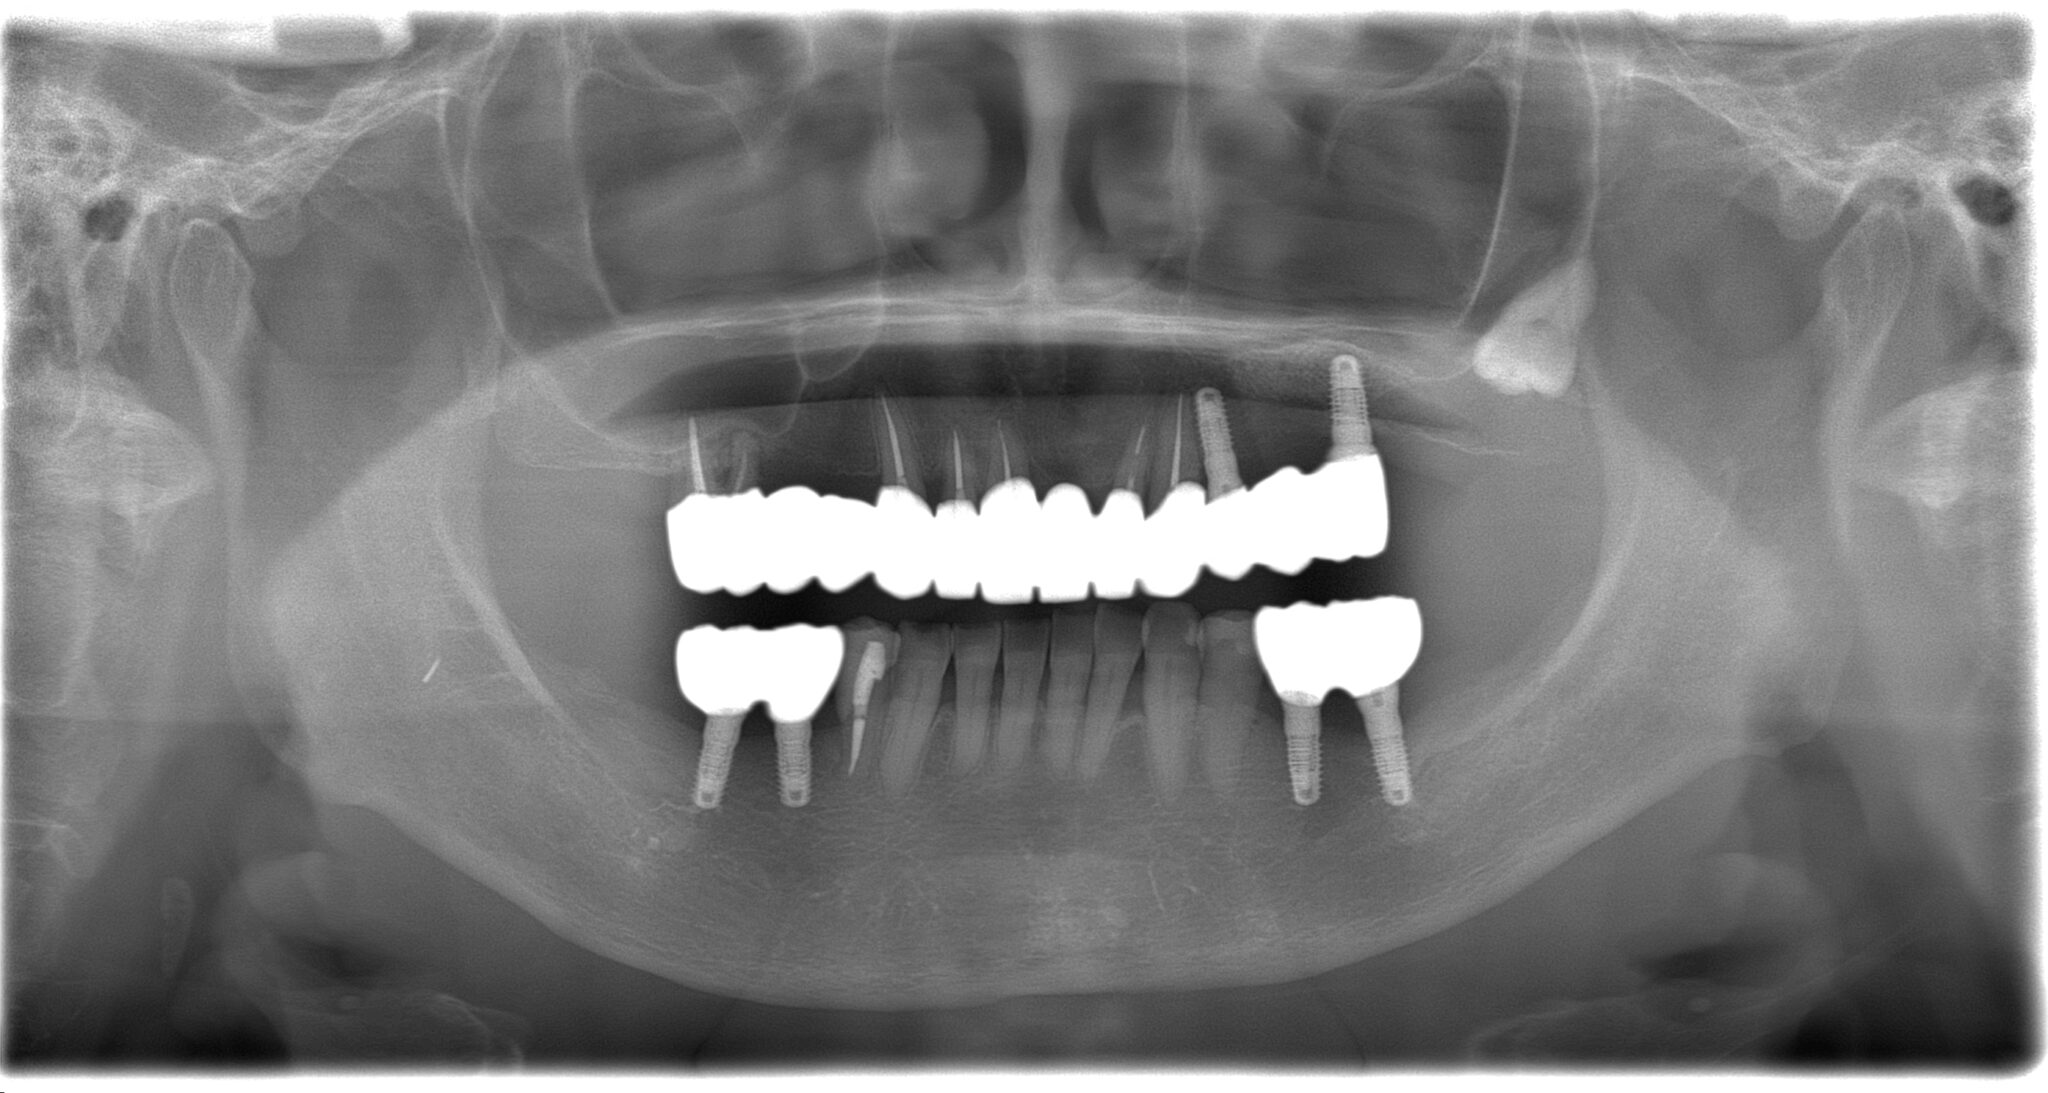

| 診断名・ 主な症状 |

臼歯部欠損 |

| 治療内容 | インプラント埋入(左下5・6,右下5・6,左上4・6) サイナスリフト(左上4・6) ジルコニアBr(右上6−左上3) E –MAX CAD(右下4) セラミックインレー(左下4) |